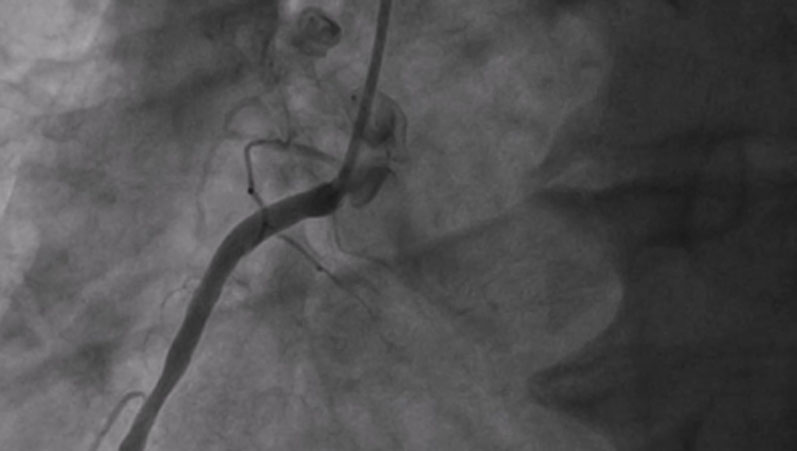

PCI, ECMO+IABP and mitral repair: interventional treatment in a HFrEF patient